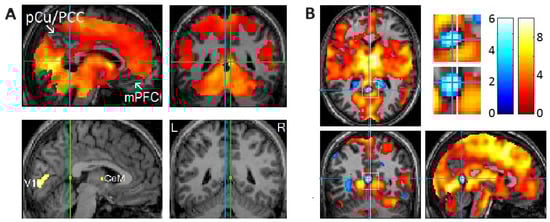

- Hong, C.C.-H.; Harris, J.C.; Pearlson, G.D.; Kim, J.-S.; Calhoun, V.D.; Fallon, J.H.; Golay, X.; Gillen, J.S.; Simmonds, D.J.; van Zijl, P.C.M. fMRI evidence for multisensory recruitment associated with rapid eye movements during sleep. Hum. Brain Mapp. 2009, 30, 1705–1722. [Google Scholar] [CrossRef]

- Hong, C.C.-H.; Fallon, J.H.; Friston, K.J. fMRI evidence for default mode network deactivation associated with rapid eye movements in sleep. Brain Sci. 2021, 11, 1528. [Google Scholar] [CrossRef]